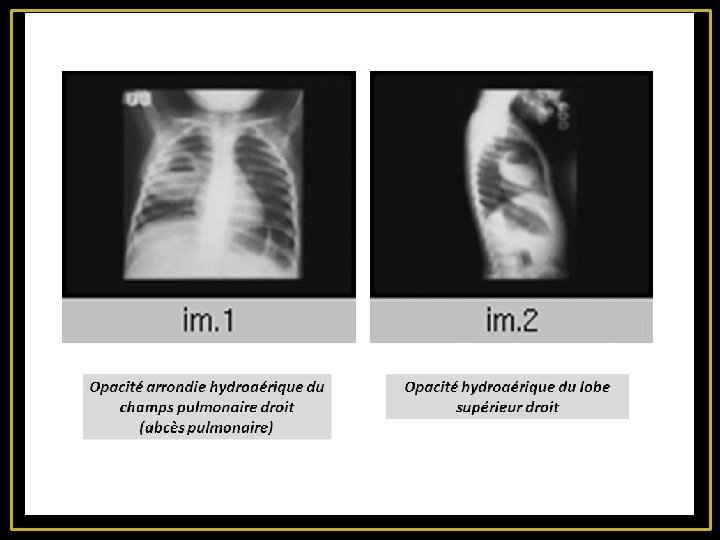

Abcès pulmonaire - Cavité (unique ou multiple) remplie de pus, secondaire à une nécrose du parenchyme pulmonaire - Se développe généralement au sein d'un foyer pneumonique - La fréquence de la cavitation dépend de la nature du germe (++ staphylocoque, les germes aérobies à Gram négatif et les germes anaérobies - Paroi : limite interne irrégulière La TDM permet de différencier un abcès pulmonaire d'un empyème : À la différence de l‘abcès, l’empyème, est ovale à paroi fine et régulière, se raccordant à la paroi à angle obtus et comprime le parenchyme voisin